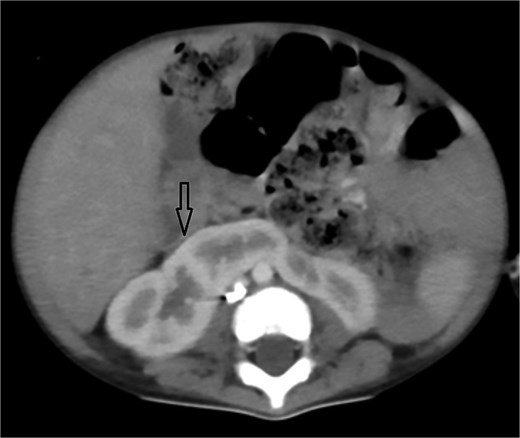

Urgent transthoracic echocardiography demonstrated a large echodense mass in the right hemithorax, compression of the right atrium and reduced flow through the right-sided shunt. Computed tomography angiography (CTA) confirmed a massive saccular pseudoaneurysm (≈8 × 7 × 6 cm) arising from the anastomosis between the right subclavian artery and the mBTTS graft, completely thrombosed without active contrast extravasation (Fig. 1). There was complete thrombotic occlusion of the right pulmonary artery, right lung collapse due to extrinsic compression and right lower-lobe consolidation consistent with pneumonia (Fig. 2). CTA also revealed left isomerism with central liver and polysplenism (Fig. 3) and a horseshoe kidney (Fig. 4), suggesting a previously unrecognized polymalformative syndrome.